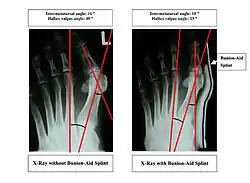

Bunions can be diagnosed and analyzed with a simple x-ray, which should be taken with the weight on the foot.[10] The hallux valgus angle (HVA) is the angle between the long axes of the proximal phalanx and the first metatarsal bone of the big toe. It is considered abnormal if greater than 15–18°.[11] The following HV angles can also be used to grade the severity of hallux valgus:[12]

- Mild: 15–20°

- Moderate: 21–39°

- Severe: ≥ 40°

The intermetatarsal angle (IMA) is the angle between the longitudinal axes of the first and second metatarsal bones, and is normally less than 9°.[11] The IM angle can also grade the severity of hallux valgus as:[12]

- Mild: 9–11°

- Moderate: 12–17°

- Severe: ≥ 18°